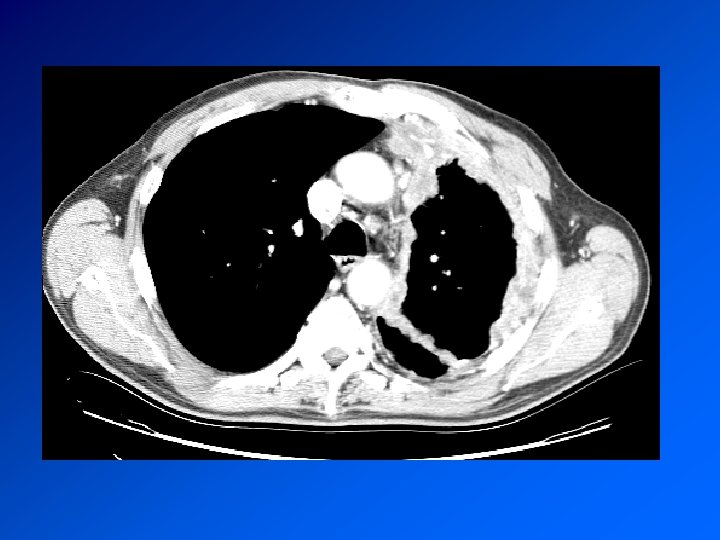

Enquête diagnostique Histoire de la maladie : recherche une maladie déjà connue, une exposition à un toxique professionnel, la prise de médicaments Examen clinique retrouve le syndrome pleural. Recherche de signes d’autres maladies associée Radio de thorax : fait le diagnostic TDM Thorax : précise les images Ponction pleurale oriente en fonction de la cytologie

Mésothéliome pleural Cancer primitif de la plèvre Principal facteur de risque (retrouvé dans > 80% des méso): exposition à l’AMIANTE CDD : AEG douleur, syndrome pleural. Surveillance d’un sujet exposé Radio : pleurésie. Epaississement tumoral nodulaire de la plèvre. Extension extrathoracique rare mais possible Evolution défavorable. Survie moyenne 9 à 12 mois. Traitement décevant : chimiothérapie. Radiothérapie sur orifices biopsies et drainage Symphise pleurale